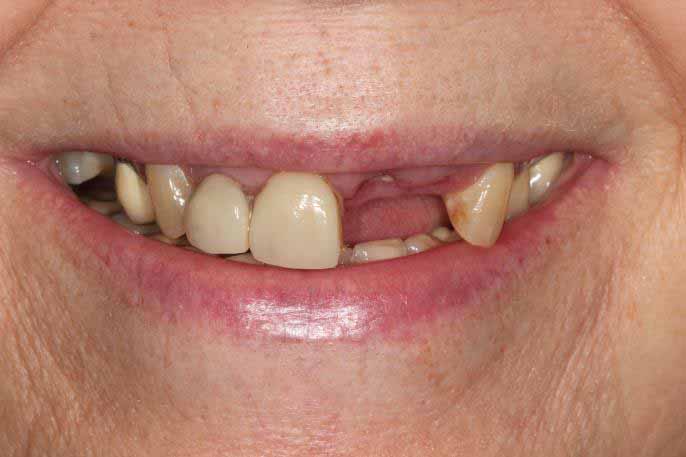

Full mouth Treatment – missing upper front teeth and mispositioned implants in the Lower left side meant planning was key here to get the desired result. Implants were placed to replace the missing teeth, veneers/crowns on the remaining upper teeth allowing an improvement in overall shape and colour, and the implant crowns on the lower left were change to bring into the line of the bite.